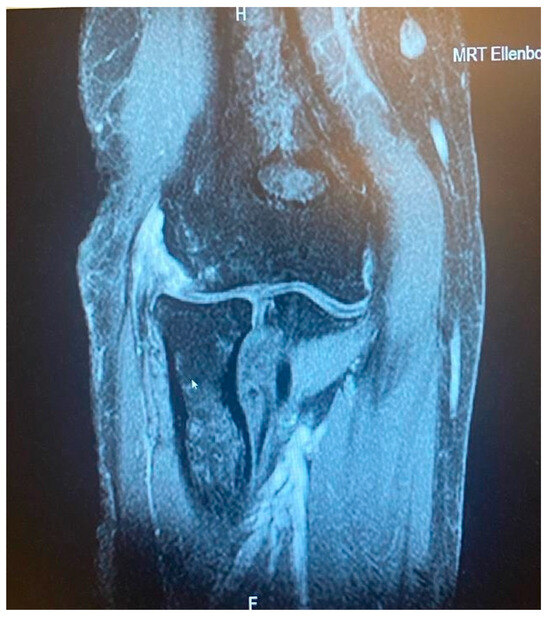

- It is contingent on the integrity of the CEO, whether it is intact, has a moderate or extensive partial tear, or is completely ruptured with or without retraction. This evaluation can be conveniently conducted via MRI.